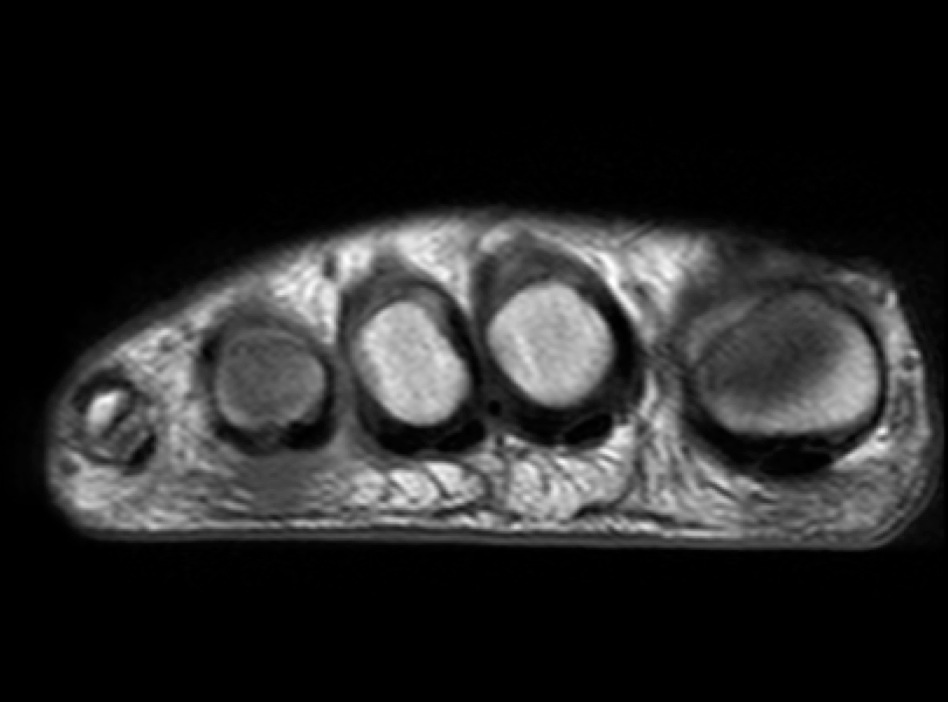

Figure 2 for case Advential bursitis

Figure 2